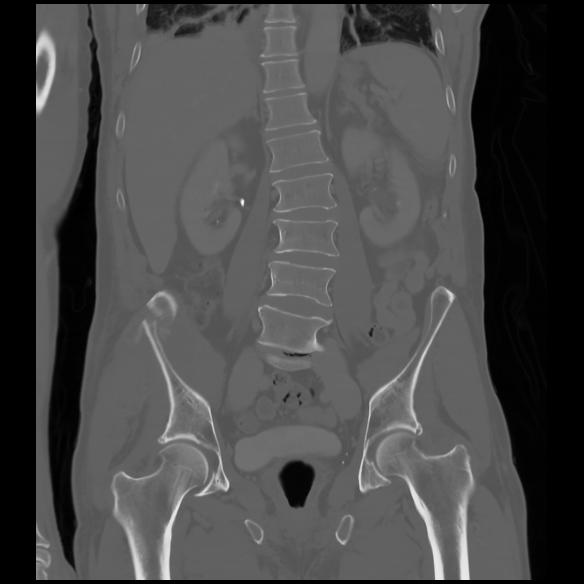

6 CUERPO,CE,Coronal,3.000,CUERPO,Coronal,